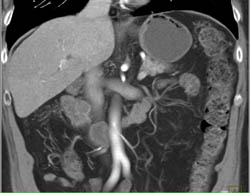

Polycystic Liver Disease